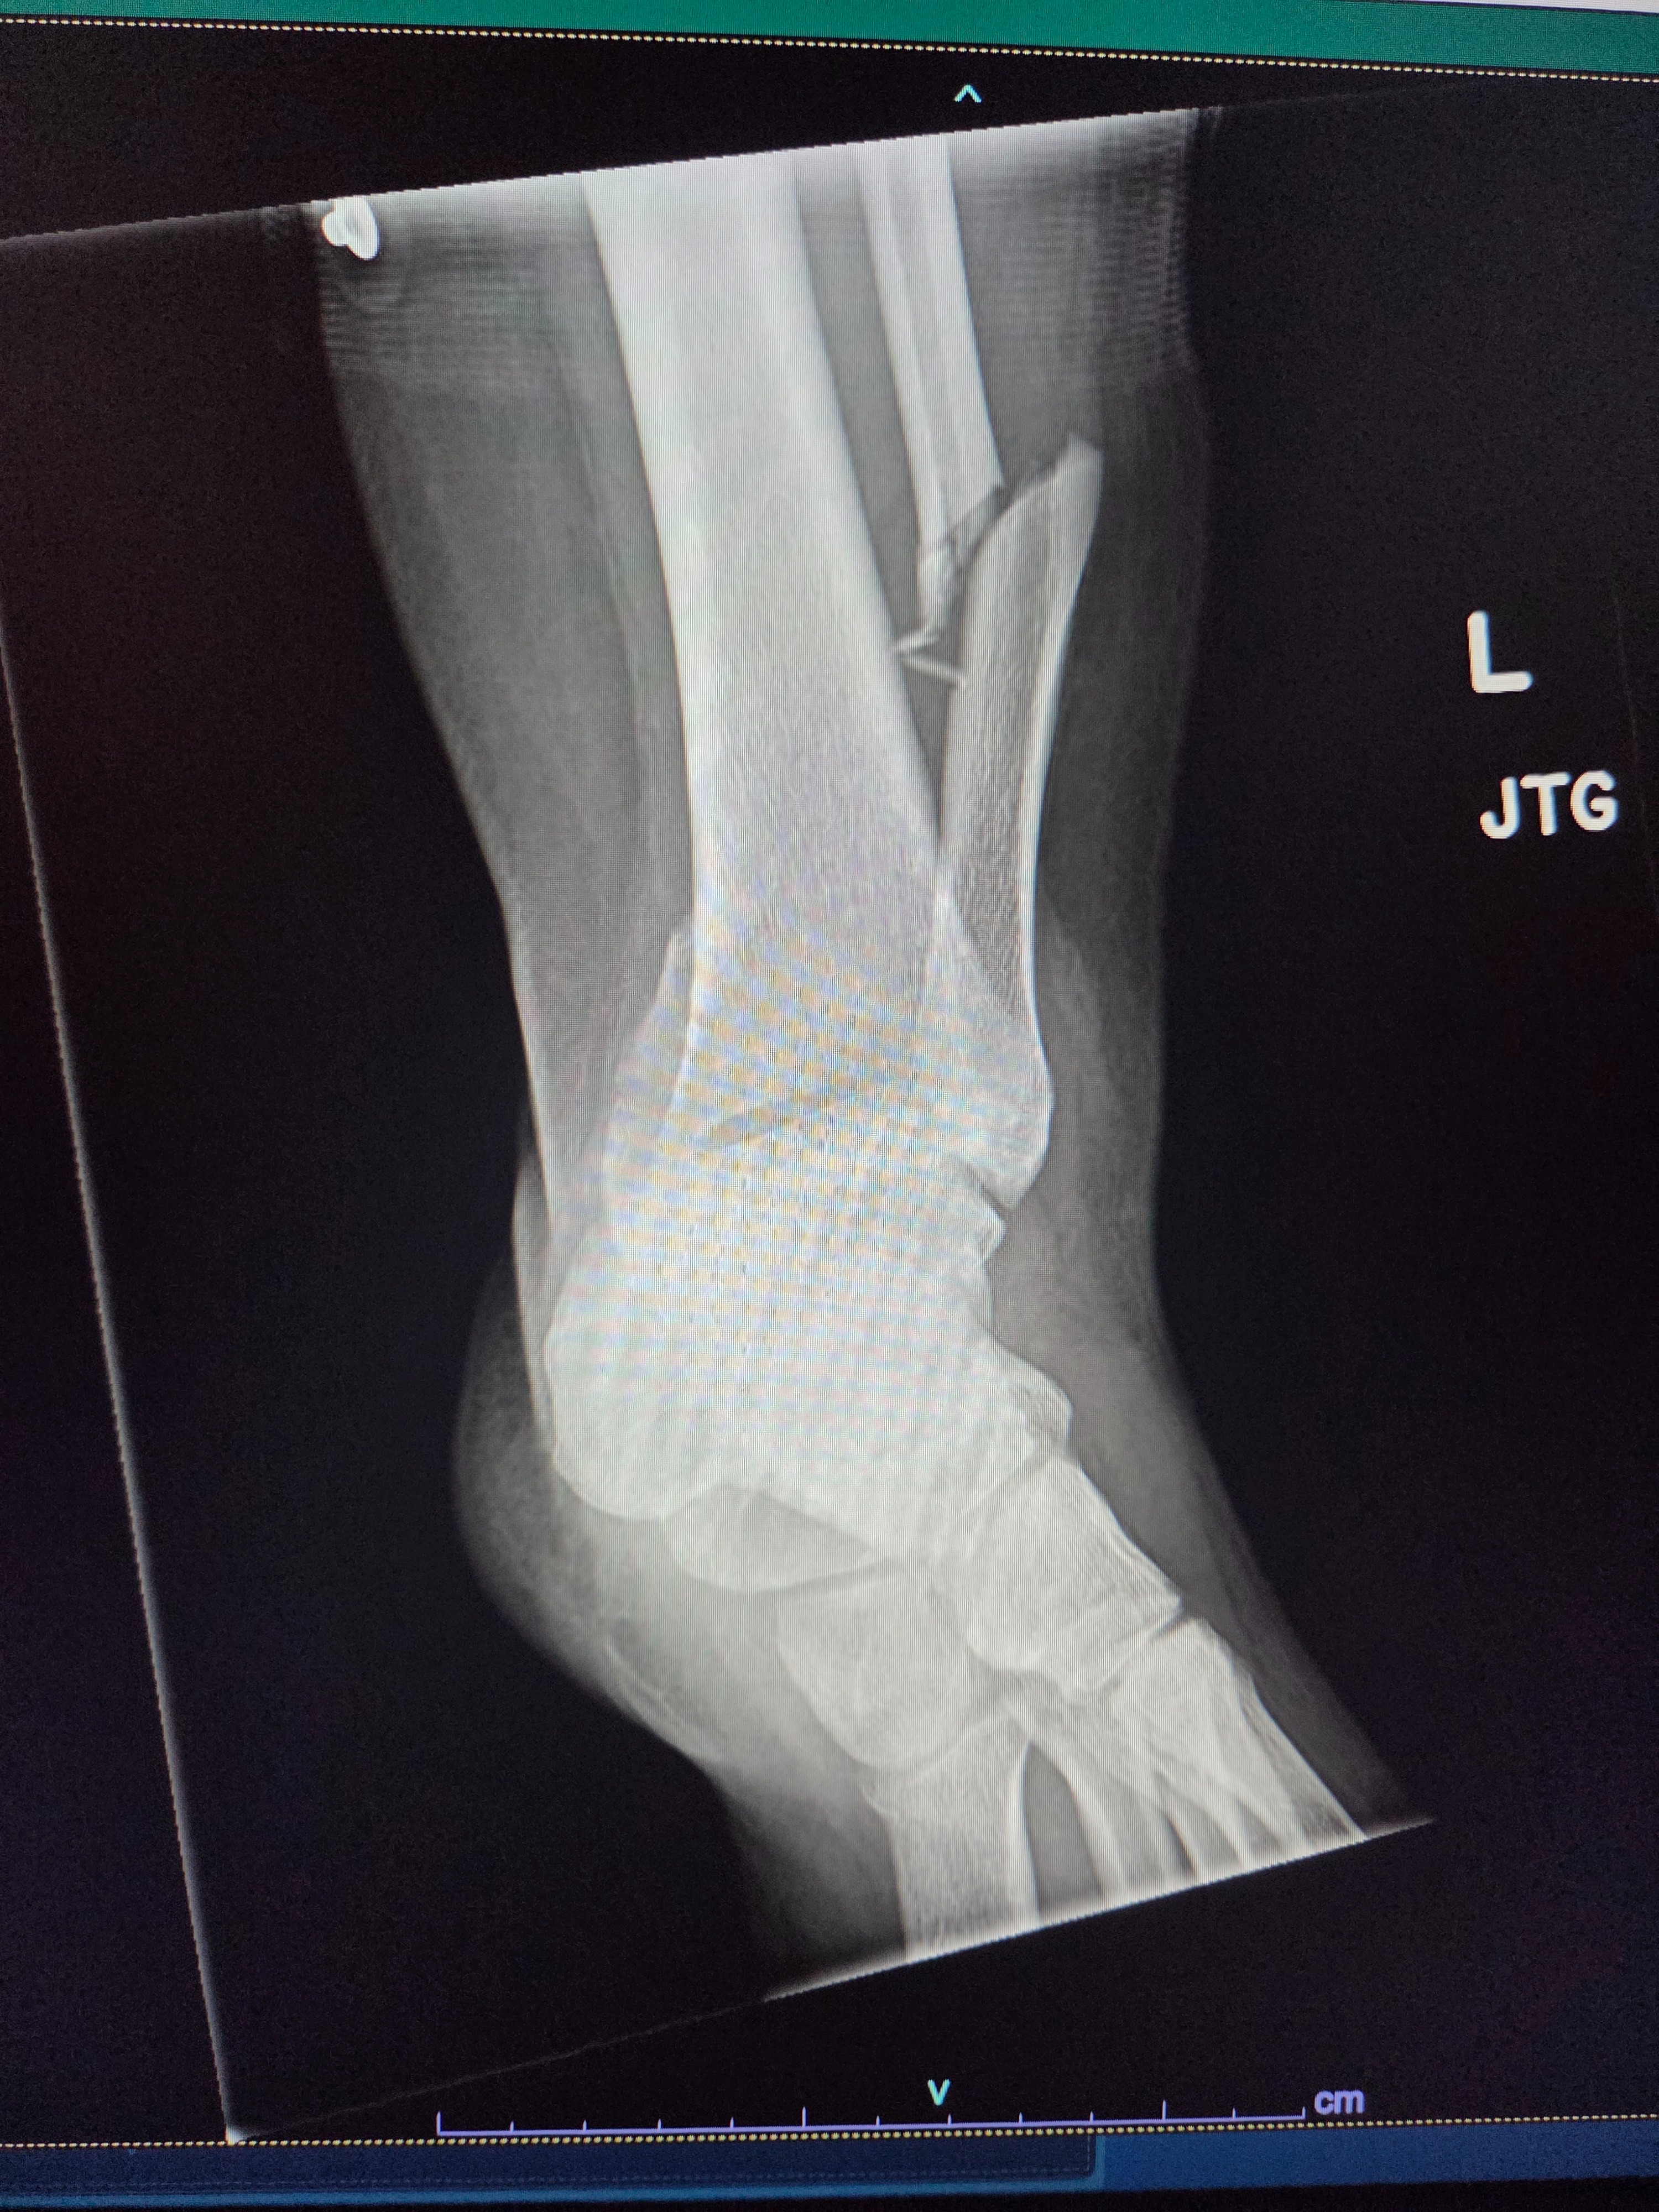

Hi! I'm Ashlie and just had the craziest day of my life. Tuesday, September 9th 2025 my car was involved in a hit and run and when I went outside to go look at the damages, I fell from our front porch and fractured and dislocated my ankle. I'm co-owner of The Paw Spa in Fallon and will continue to work to the best of my abilities but any help with medical bills would be greatly appreciated.